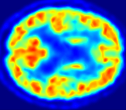

4.0.2 Qualitative Results

Looking at sample synthetic PET images in Fig. 3, it can be seen that all of the models are able to make reasonable predictions. The outputs of the U-PET and U-PET (no att.) look very similar and are smoothed compared to the input. The pix2pix predicts more details, which seem to be important for the discriminator. However, even though this model has finer predictions, the intensity values are worse compared to the U-PET and U-PET (no att.) as seen in Fig. 2; an example is given in Fig. 3 in the second row.

From a clinical perspective, the synthetic generated PET show a smoother version of the real PET images but keep the same pattern of FDG uptake, especially, hypometabolism in the respective brain areas. This backs up our hypothesis, that MRI contains information that correlates with the functional information of PET images. Moreover, the synthetic PET could be used as complementary visualization for physicians beyond the task of classification.

In Fig. 4, the attention maps of the U-PET are shown for multiple examples. On the one hand, the attention map of the skip connection (AttMap skip) highlights details of the brain structure, which is in agreement with the assumption that the network has to transform the specific structures of the MRI scan into the PET modality. On the other hand, the attention gates used for the classification task rather focus on more specific regions. One can observe a trend that the attention maps used for classification tend to highlight regions which have a low uptake in the PET. Since areas with a lower uptake in the PET correspond to areas with lower functional activity (hypometabolism), this focus area of the network seems reasonable with respect to the classification task.